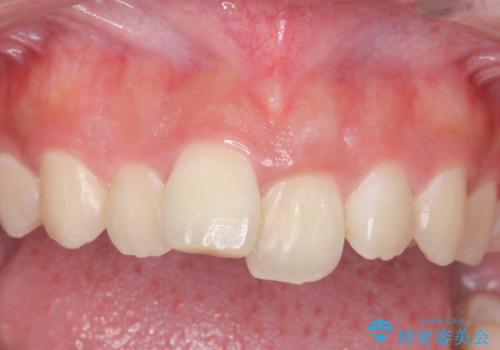

前歯の角度や歯ぐきのラインに差が大きかったため、やむなく神経をとり、歯ぐきの手術を行い出来るだけ歯ぐきのラインを整えるようにしました。

手術をしなければ左上1番の歯ぐきのラインは左上2番よりも下にきてしまい、長さの短い歯になってしまうところでした。

笑っても大きく歯ぐきが見える方ではなかったので、歯ぐきのラインが目立つことはなかったです。

手術をしなければ左上1番の歯頚ラインは左上2番よりも短い位置になっていたため、歯自体の長さが不自然なほど短くなってしまったと思います。